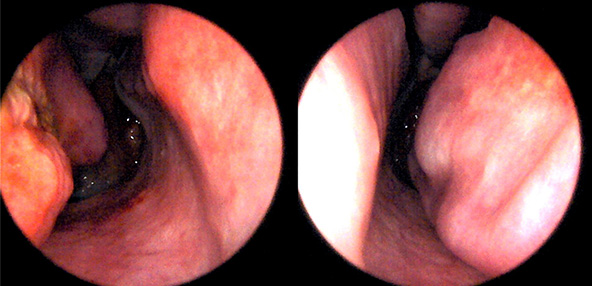

본 사진은 의료기관에서 진료를 본 환자이고, 전후 사진 인물이 동일인이며,동일조건에서 촬영이 되었습니다.